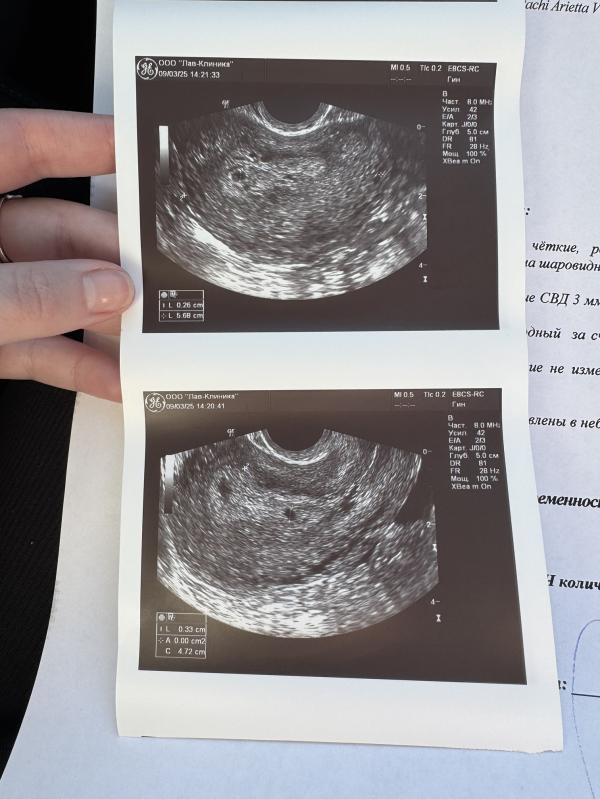

Привет! У кого-то может была похожая история? Была на узи в воскресенье 9 марта, по последней менструации 5 недель, но на узи еле увидели плодное яйцо, сказали сдать ХГЧ и через 2 недели повторить узи. В понедельник 10 марта сдала ХГЧ, результат - 2500 МЕ. Почему тогда на узи так плохо было видно? Может быть такое, что аппарат узи был плохой?